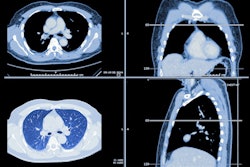

A team of researchers from Noordwest Ziekenhuisgroep in Alkmaar, the Netherlands, retrospectively reviewed 300 patients receiving a follow-up CT exam for an incidentally detected lung nodule. Preliminary results from over 100 patients showed that nearly 20% could have been safely discharged from follow-up based on nodule volumetric analysis by a commercial AI software application.

In their recent study, the researchers sought to determine whether using AI to automatically detect and measure pulmonary nodules could lead to earlier discharge from follow-up for cancer screening. They retrospectively gathered a cohort of 300 patients who received CT screening for follow-up of pulmonary nodules in 2020.

Version 3.9.3 of Veye Lung Nodules (Aidence) had been applied then to the CT studies, but the volume measurements were not used to discharge patients earlier from screening follow-up, Gimbel said. The software was set at an operating point of 0.85, as well as a filter of 4 mm to detect all nodules 4 mm and larger.